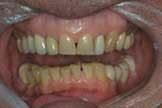

Let me cite a real-life case as an example. (The full-face photo in this case is eliminated for the sake of the patient's privacy.) As we — the patient, my assistant, and I — reviewed the pictures, the patient first noted the brightness of the old porcelain fused to metal crown on his lateral incisor. Then, in the close-up smile photo, he noted the contrast between that tooth and the cuspid behind it. (Figure 1). When he saw the retracted view, it was obvious even to this nondentist that there was something very wrong with his lower plane of occlusion. (Figure 2). He also noticed the exposed PFM margins. This allowed us to explain how the supra gingival margins of Empress restorations would not develop this problem down the road. In the upper occlusal photo, the hole in the crown and the fractured crowns were very apparent, as was the wear and old fillings on his front teeth. (Figure 3.) The wear and irregularities of the lower teeth were also obvious to him. (Figure 4.)